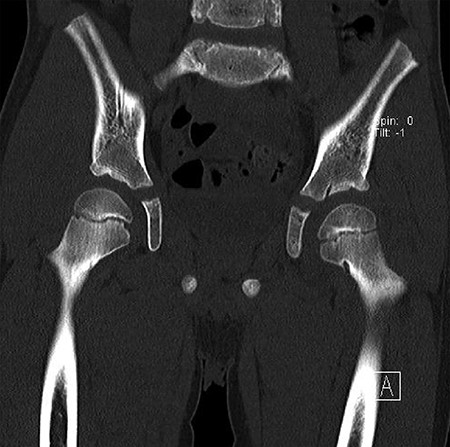

CT hips reported a well-defined lesion seen bilaterally in the neck of femur anterior infero-medial aspect, more prominent on the left side measuring 7 x 3 mm on left side both in coronal (Fig. 3) and axial (Fig. 4) views. On the right side, other lesion measuring 2 x 1 mm (Fig. 5) seen in coronal view. These two lesions are well defined with a sclerotic border with a small cortical defect. The lesion shows fat density. The symmetrical appearance of the lesion combined with the fat density and location suggest the diagnosis of synovial herniation pit. MRI Pelvis revealed minimal left hip joint effusion with loculated fluid seen along the trochanteric bursa with the largest measuring 0.9 x 1.5 cm (Fig. 6, 7).

Sowed coronal cut of CT hips demonstrating the synovial pit on left and right side.

Showed coronal cut of CT hips demonstrating the synovial pit prominent right side.